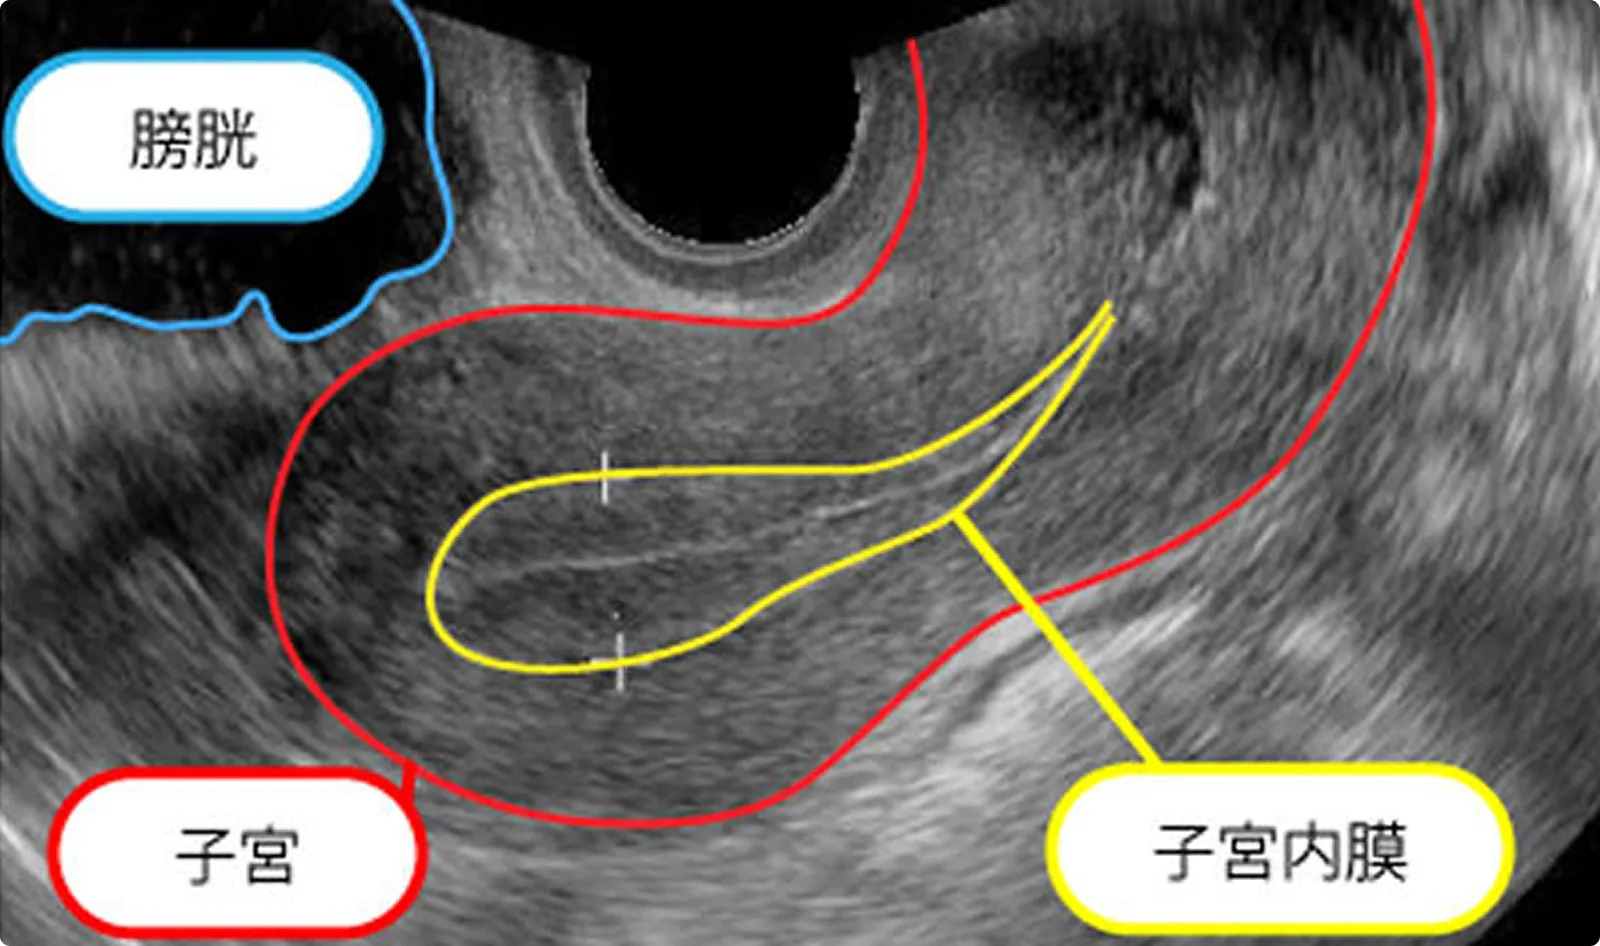

排卵直前

排卵直前の子宮内膜

腺上皮も間質細胞も増殖し、腺腔分泌物も増え3層に見えます。